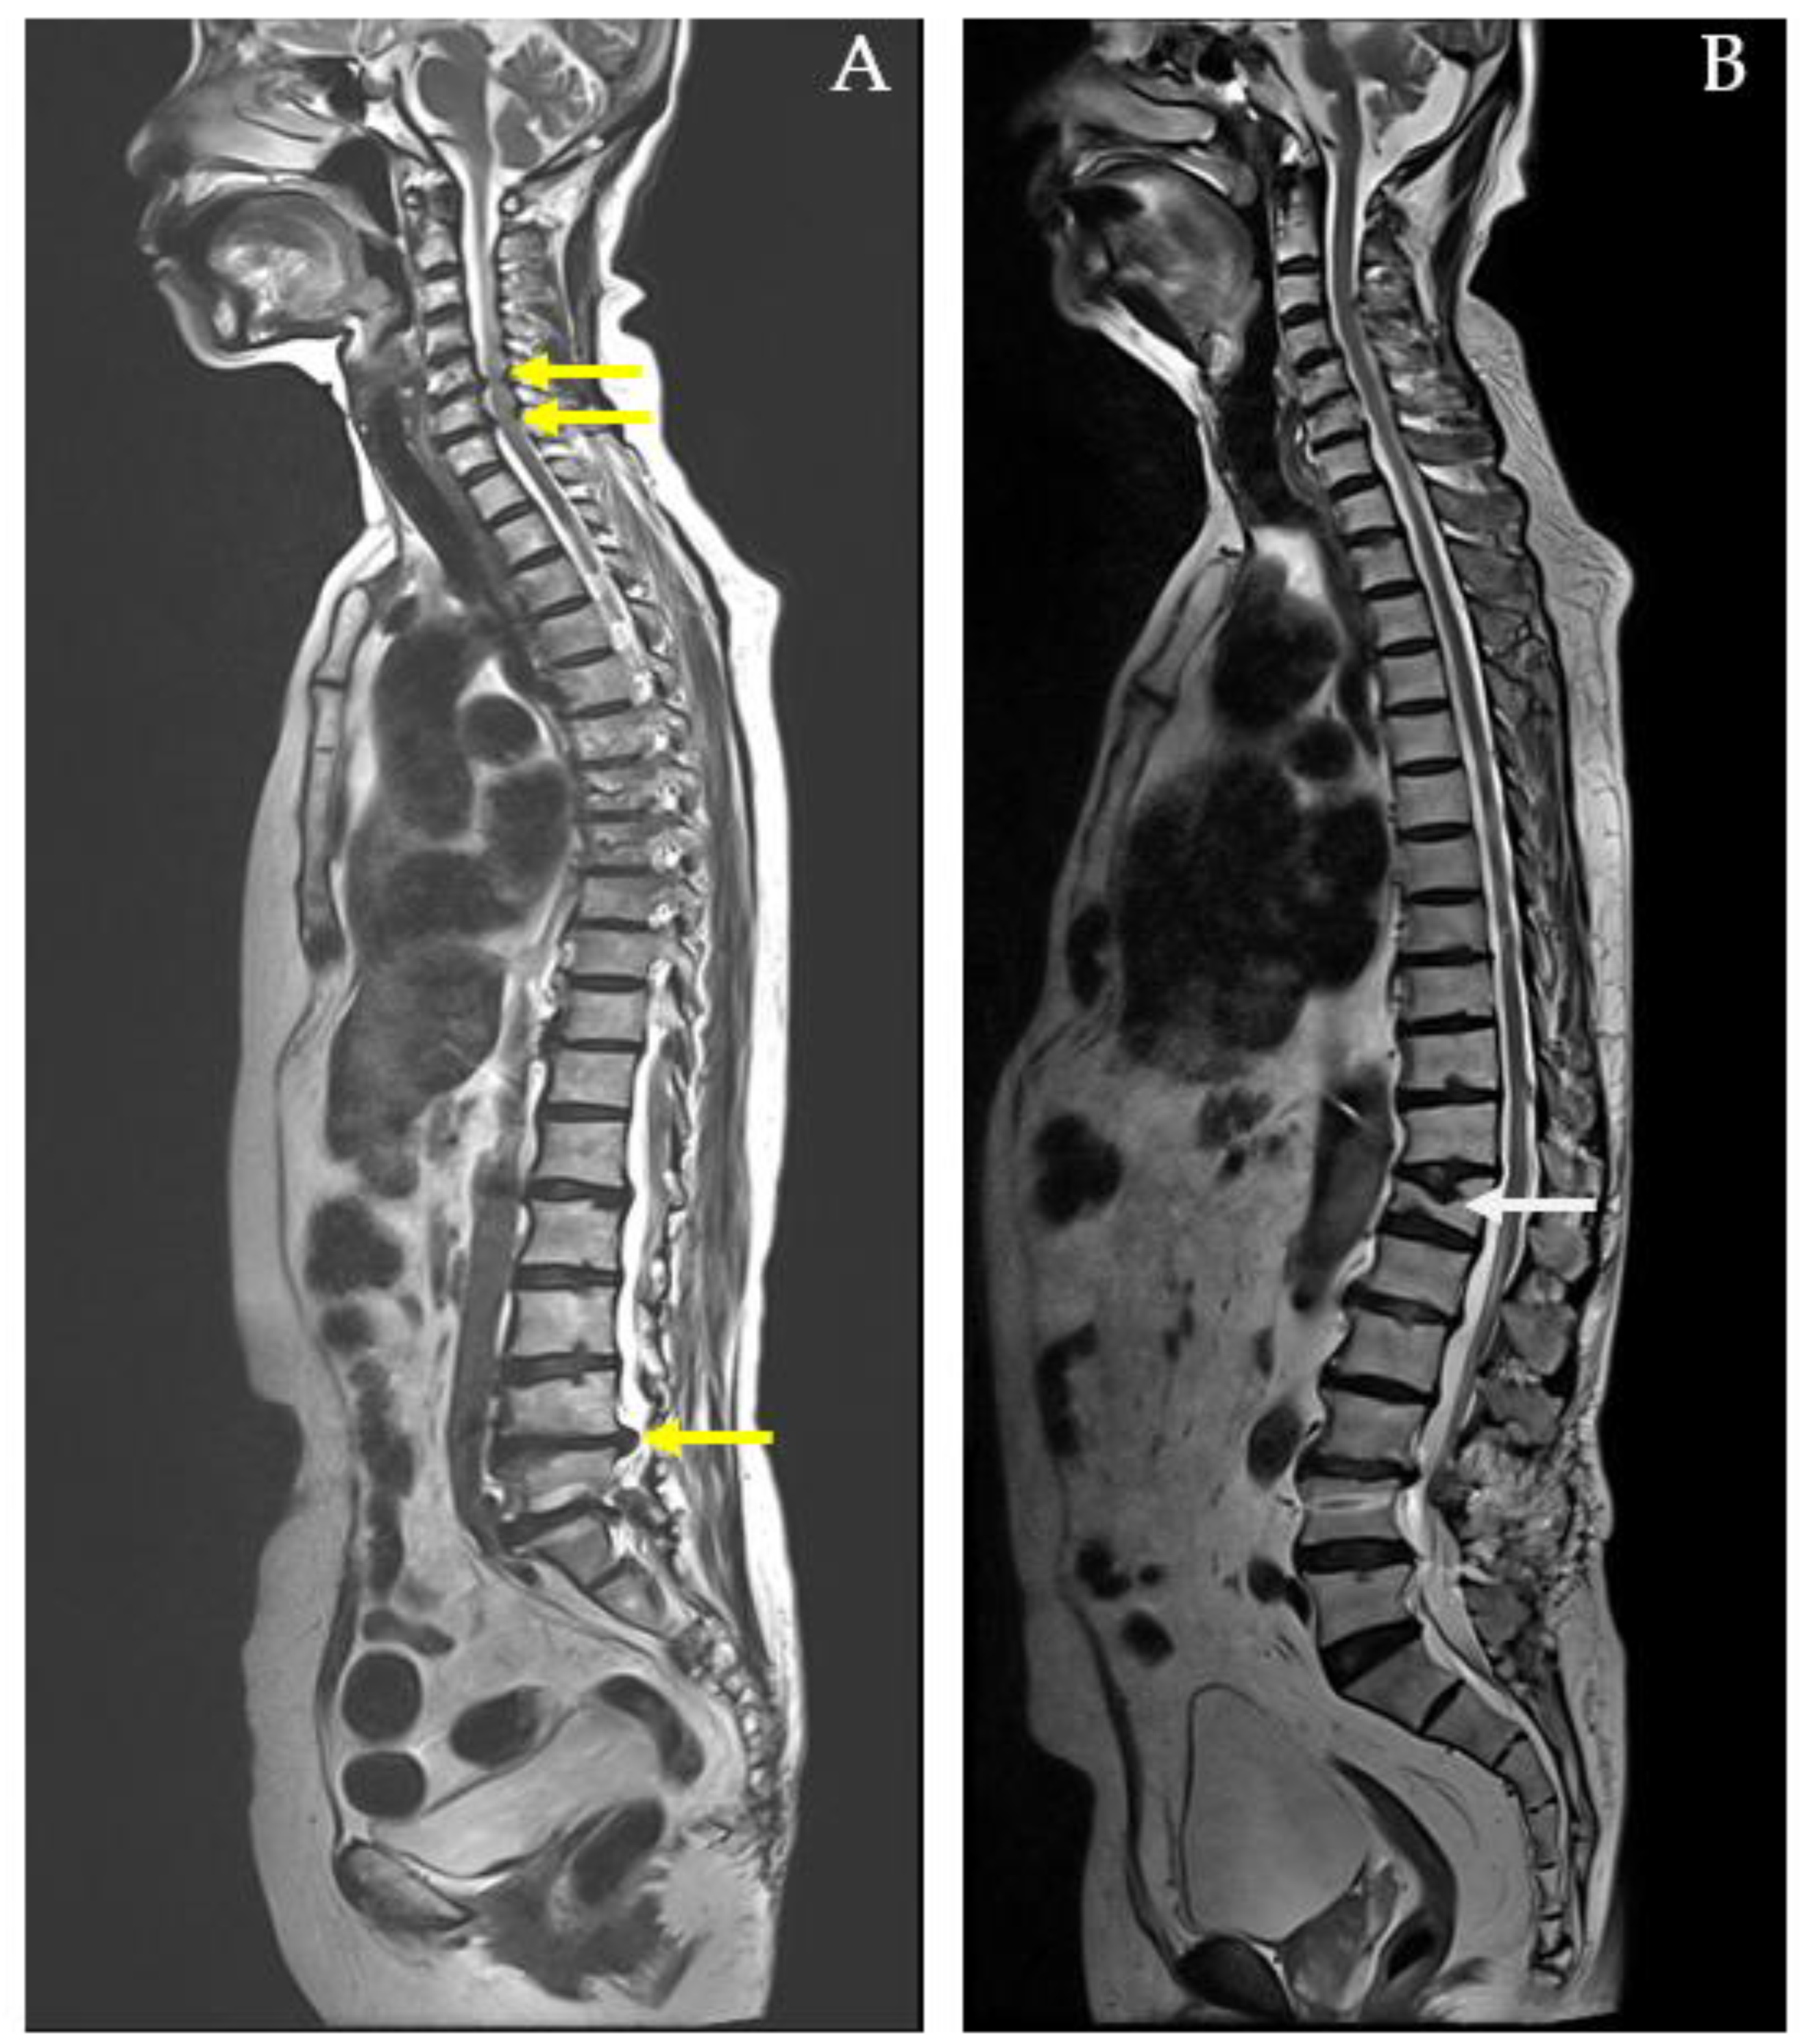

Number of Spine Pain Regions: The number of painful regions in the spine was assessed using the MRI report, which offers an objective measure of pain distribution and severity. This clinical examination identifies areas of tenderness and helps differentiate between conditions involving localized versus widespread spinal involvement. For example, a 73-year-old female with herniated intervertebral discs (HIVDs) at the C5-C6-C7 and L4-L5-S1 levels had six identified spine pain regions (Figure 2A). In contrast, a 77-year-old male with a compression fracture at T12 had only one identified spine pain region (Figure 2B).

Figure 2. MRI whole-spine imaging demonstrating herniated intervertebral discs (HIVDs) indicated by yellow arrow in (A) and compression fracture indicated by white arrow in (B).